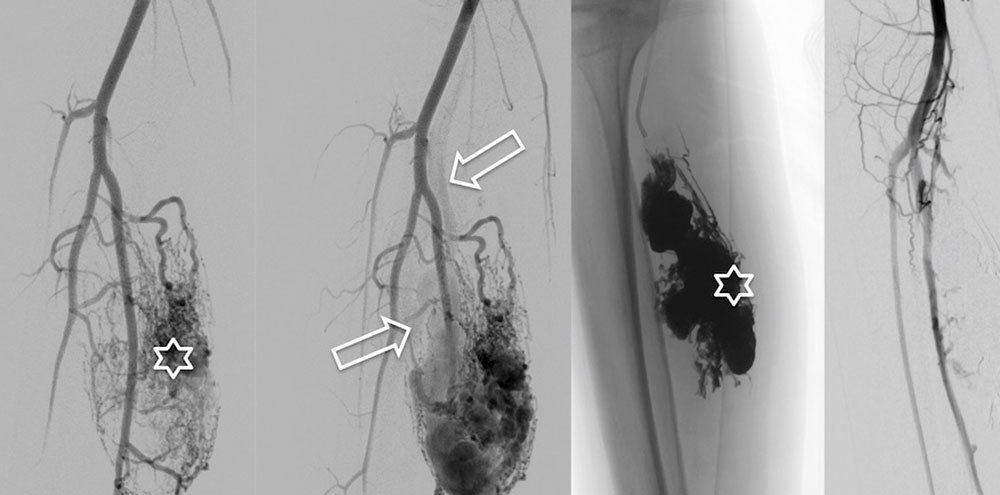

To eliminate an arteriovenous fistula as well as the shunts or the nidus of an arteriovenous malformation, endovascular therapy is normally the first choice. Relatively new techniques are available for this purpose with positive results regarding the long-term course of the disease. Depending on AVM localization and extension, these endovascular techniques can in some cases be combined with subsequent surgical resections (especially if there is a nidus with multiple fine fistulas). Primary resection of an arteriovenous malformation is usually not technically possible. The goal of endovascular treatment must always be selective and complete occlusion of the nidus while sparing the surrounding tissue. Endovascular occlusion of feeder arteries (e.g., with coils and plugs), proximal embolization or surgical ligation of feeder branches can often produce a temporary improvement, but this is later followed by worsening of symptoms due to the formation of new feeder arteries supplying the nidus and true proliferation of the lesion. A long-term therapy plan usually comprises several treatment sessions. Incomplete occlusion of the nidus leads to expansion of the arteriovenous malformation in the course of the disease and should therefore be avoided.

Percutaneous or endovascular embolization is still the therapy of choice. The nidus and the early drainage veins of the arteriovenous malformation are closed with permanent liquid embolic agents via a transarterial access and angiography. The liquid embolics are ethylene-vinyl alcohol copolymers, n-butyl cyanoacrylate (nBCA) or pure high-percentage ethanol.

The administration of these embolic agents requires a great deal of operator experience, since the arterial supply of the surrounding, unaffected tissue must be protected and displacement of embolic agents into healthy vessels must be avoided. If the angioarchitecture of the arteriovenous malformation permits, i.e., only a few drainage veins are present, embolization via a retrograde transvenous approach or a direct percutaneous approach is a very promising alternative. If it is technically and anatomically possible to completely occlude an arteriovenous malformation by embolization, a subsequent complete resection of the occluded nidus should be discussed. Additional resection of the occluded nidus may prevent recurrence in the long term. Additionally, resection may remove the remaining embolic material if it has a space-occupying effect.